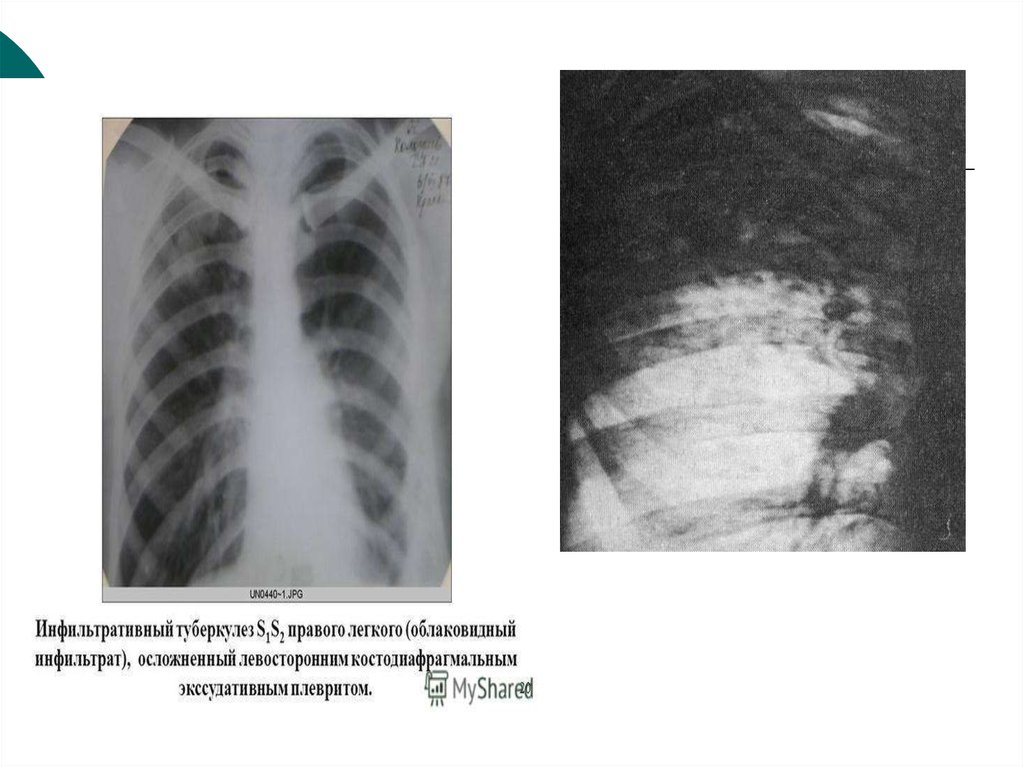

Симптомы и лечение инфильтративного туберкулеза легких

Раздел: Снимки-откровения